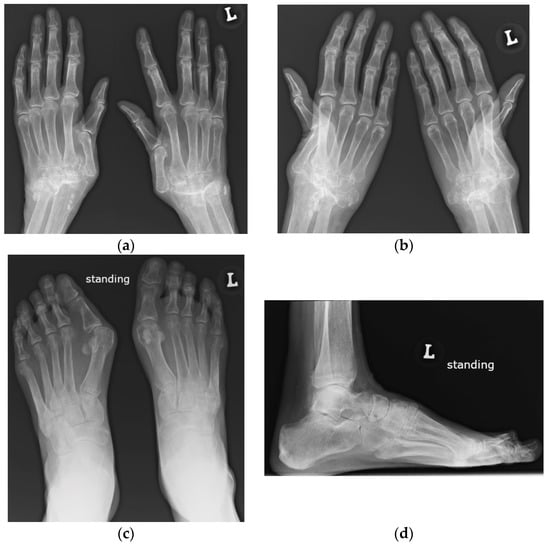

Figure 12.

Magnetic resonance (MR) imaging of the femoral head osteonecrosis (ON) in a 14-year-old female with juvenile systemic lupus erythematosus. (a) Coronal and (b) axial proton density-weighted with fat saturation (right) MR images of the pelvis and right hip show a geographic serpiginous lesion in the right femoral head, with a bone marrow edema irregular contour and demarcation line consistent with ON (arrow).